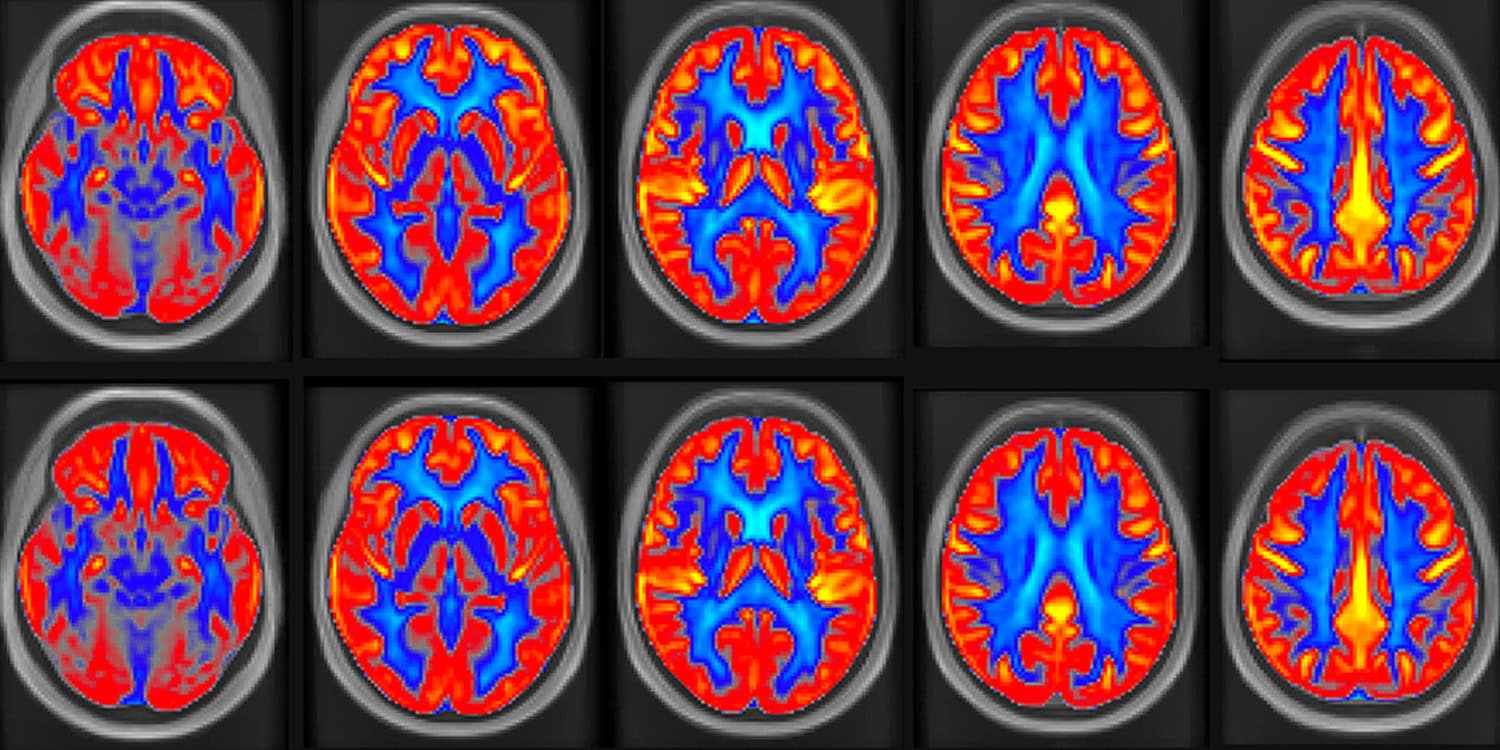

The primary measure for the study was cerebral blood flow, assessed using a non-invasive imaging technique called pseudo-continuous arterial spin labeling magnetic resonance imaging. This advanced method allows researchers to quantify the amount of blood reaching brain tissue without the use of radiation or contrast dyes.

The imaging results revealed a statistically significant improvement in brain vascular responsiveness following the peanut intervention. Global cerebral blood flow increased by 3.6 percent compared to the control period.

When the analysis focused specifically on gray matter, which contains the cell bodies of the brain’s neurons, the increase in blood flow was 4.5 percent. The researchers observed regional improvements as well. Blood flow increased by 6.6 percent in the frontal lobes and 4.9 percent in the temporal lobes. These areas of the brain are intimately involved in processing memories, language, and executive control.